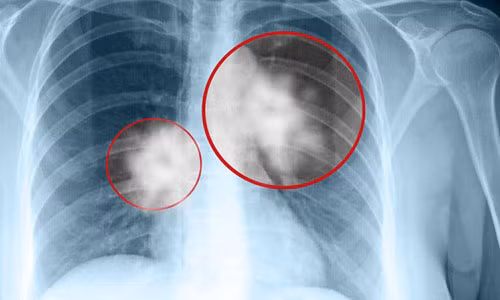

| Ung thư phổi là căn bệnh ngày càng phổ biến. |

Ung thư phổi có 2 loại chính. Thứ nhất là ung thư phổi tế bào không nhỏ, chiếm tỷ lệ khoảng 85 đến 87% tổng số ca. Với đặc điểm phát triển chậm hơn so loại còn lại nên có đến 40% trường hợp được chẩn đoán phát hiện bệnh thì ung thư đã lan đến các bộ phận khác của cơ thể. Thứ hai là ung thư phổi tế bào nhỏ, chiếm tỷ lệ khoảng 13% đến 15% tổng số ca. Ung thư này hoạt động rất mạnh và lan truyền nhanh, hầu hết các trường hợp được chẩn đoán đều đã ở giải đoạn nặng, khối u di căn đến các bộ phận khác của cơ thể.

Các nghiên cứu cho thấy hút thuốc lá là nguyên nhân phổ biến nhất gây ung thư phổi. Triệu chứng thường gặp là ho dai dẳng. Chụp X-quang ngực có thể phát hiện, nhưng cần phải làm thêm xét nghiệm chẩn đoán hình ảnh và sinh thiết để kiểm chứng. Phẫu thuật, hóa trị và xạ trị đều có thể được sử dụng để điều trị ung thư phổi.